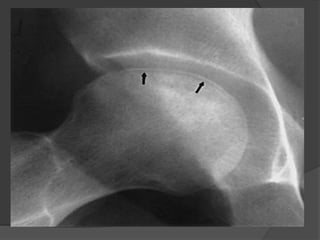

AP radiographic view of the pelvis shows flattening of the outer portion of

the right femoral head from avascular necrosis, with adjacent joint space

narrowing, juxta-articular sclerosis, and osteophytes representing

degenerative joint disease (stage IV)

AP radiographic viewof the pelvis shows flattening of the outer portion of the right femoral head from avascular necrosis, with adjacent joint space narrowing, juxta-articular sclerosis, and osteophytes representing degenerative joint disease (stage IV)